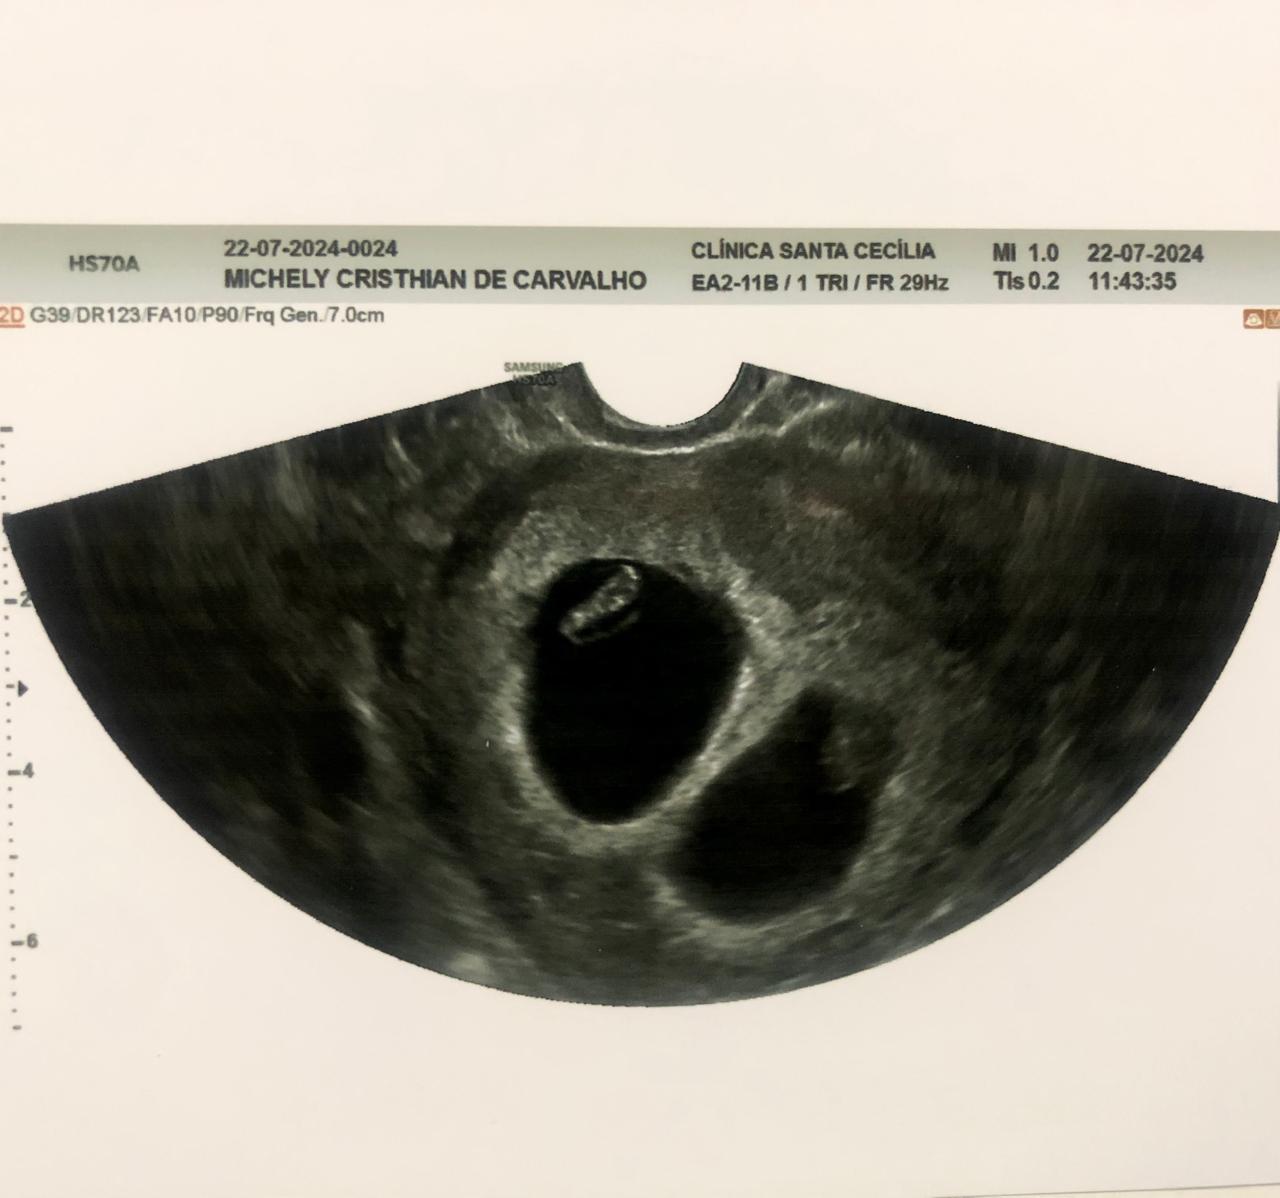

A primeira reação foi de espanto. Depois aquele impulso de olhar várias vezes para o exame Beta HCG e certificar se realmente o resultado era real. Foi em meio a choque e surpresas que a candidata Michely Cristhian de Carvalho, 24 anos, descobriu que estava grávida de gêmeos fazendo exames de saúde após aprovação no concurso público para o Corpo de Bombeiros do Piauí.

“Estava na fase de fazer exames de sangue e no final do dia fazia o teste ergométrico quando o dono do laboratório me chamou e disse que meu Beta deu positivo e fiquei em choque. Eu não acreditei, estava extasiada. Logo depois tive que fazer o exame de ultrassom e veio outra surpresa de que estou grávida de gêmeos, foi um misto de muitas emoções”, contou Michely que é nutricionista e mora em Jaicós.

Michely fez concurso para soldado em 2023 e conseguiu aprovação em teste bastante disputado. Ela foi informada da gravidez quando estava com três semanas de gestação. Hoje com 27 semanas, Michely disse que é um sonho integrar o Corpo de Bombeiros do Piauí.